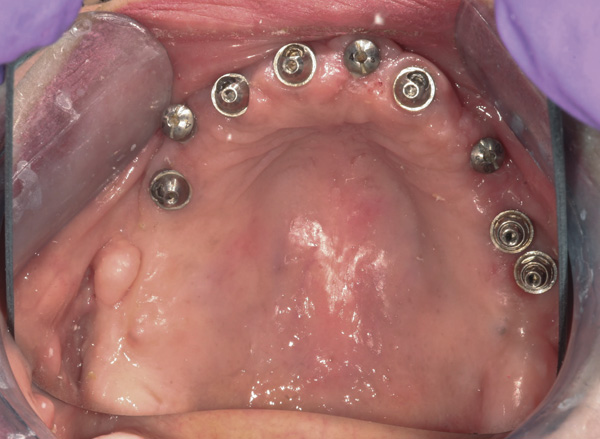

Background: This patient had a failing maxillary dentition and refused to wear a removable prosthesis. A staged approach was employed to retain some of his natural tooth abutments, and recession was noticed at the time of the impression for the second group of implants. Figure 1 shows the patient following insertion of the first set of implant custom abutments; the adjacent natural teeth are still present to support the provisional bridge. Seven months later, as shown in Figure 2, those first-stage custom abutments exhibited evidence of 1 mm to 3 mm of recession.

Figure 1 Patient following insertion of first set of implant custom abutments.

Figure 1